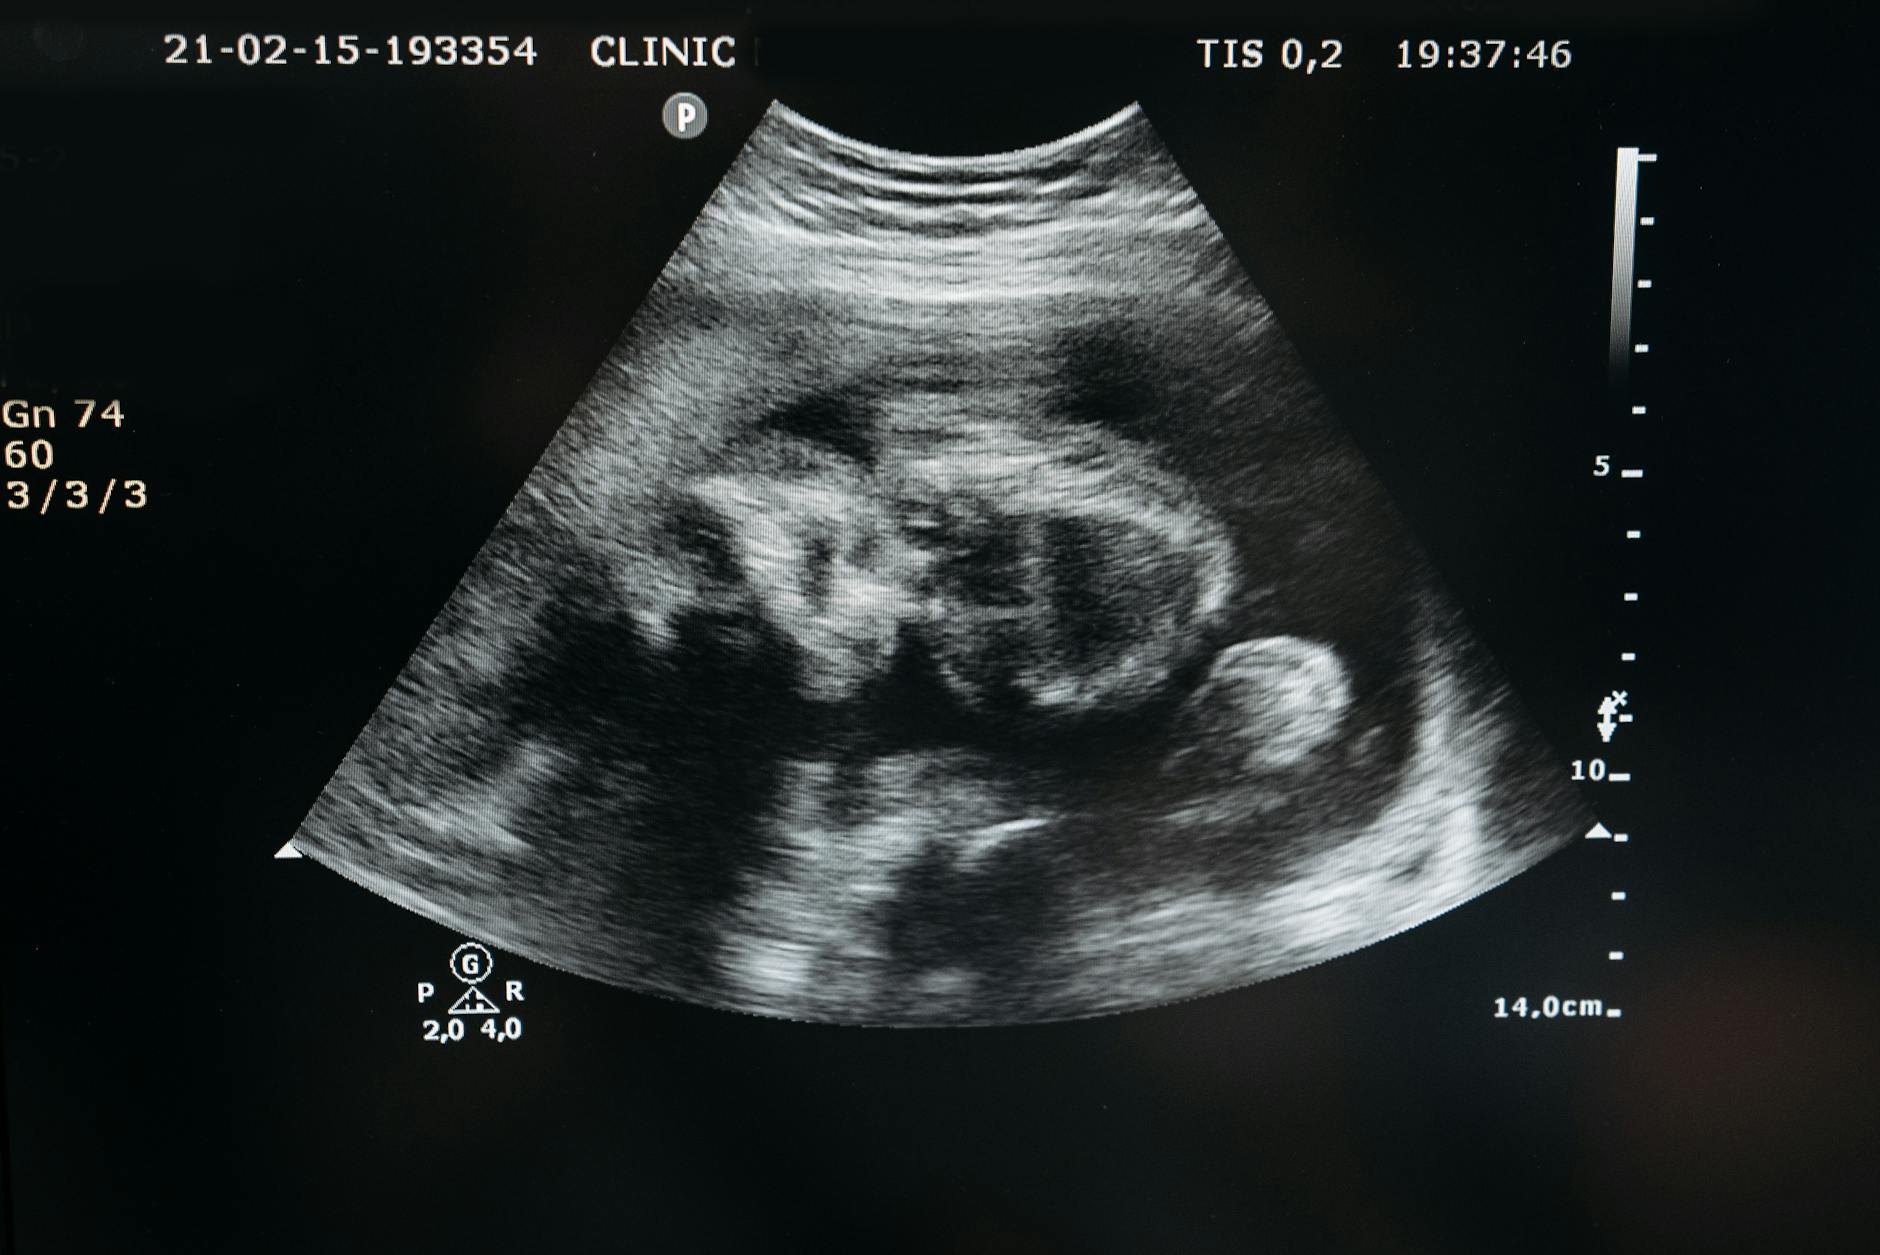

Sonda cónvex: cristales en línea pero con curvatura convexa. Mayor visión proximal que la sectorial y mayor campo de visión que la lineal. Usada en estudios abdominales, urológicos, ginecológicos e intracavitarios. Frecuencia 3–5 MHz.